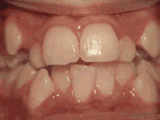

爱美之心,人皆有之~~5月份世界正畸日即将来临,暑假还远吗?分院提前给爱美的你准备好一份大大的福利,还等什么呢?抓紧约起来吧! 发现自己牙齿不整齐影响交际, 怎么还能与小伙伴愉快地玩耍? 无论是即将迈入新的年级还是即将面临找工作, 发现自己是“地包天”“龅牙妹”, 分分钟拉远自己和同龄人的距离! 这些难以启齿的牙齿问题, 想想就让人心碎,怎么办呢? 不要着急,不要慌乱! 这个时候, 你可能需要的就是牙齿矫正了~! 以下图片告诉你, 这些情况都适合去做牙齿矫正哦~! 前牙移位 症状表现:牙齿缺失、牙周疾病等导致相邻牙齿无秩序前突 牙列拥挤 症状表现:牙齿过多,牙槽骨过窄,使牙齿没有足够空间生长造成牙齿排列不齐 开颌 症状表现:通俗来讲就是咬牙时无法紧闭,上下牙齿中间有缝 上牙深覆合 症状表现:上牙边沿覆盖下牙超过1/3,俗话说的天包地 后天牙列稀疏 症状表现:疾病外因等造成的牙列稀疏,牙槽骨过长或牙齿缺失,导致排列太宽松,零零散散 前牙反合 症状表现:下牙边沿覆盖上牙超过1/3,俗话说的地包天 天生牙列稀疏 症状表现:天生的牙列稀疏,牙槽骨过长,牙缝过宽、牙齿较少(一般不缺牙),导致排列宽松,零零散散 以上几种情况有你么? 要知道一口整齐的牙齿 绝对能够把整体的颜值提升N个档次! 如果你不幸中招, 就好好利用这个正畸月, 来分院加入到正畸大军里吧! 牙齿正畸也叫做牙齿矫正,原理简单来讲呢,就是对牙齿施加一个合适的外力(一般通过矫正器来施加),这个力会通过牙齿传递到牙齿周围的牙槽骨上,使得代谢很活跃的牙槽骨发生改建,从而带动牙齿一起缓慢移动。其治疗效果有着肉眼可见的强大变化! 借此正畸月,分院为大家准备了正畸月大放价,暑假提前约的活动!!!如果还想了解更多关于牙齿矫正的信息,欢迎大家来到分院进行咨询哦~我们的专业团队会帮您定制最适合自己的矫正方案,活动月矫正方案免费送哦!定能助您改“斜”归“正”!露出灿烂自信的笑容!